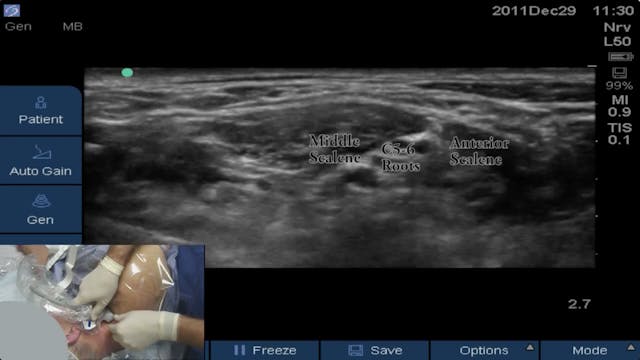

Tunneled Interscalene Catheter

Interscalene • 9m 7s

Block of the Day #5: Brandon Winchester performs an ultrasound-guided interscalene catheter at Andrews Institute